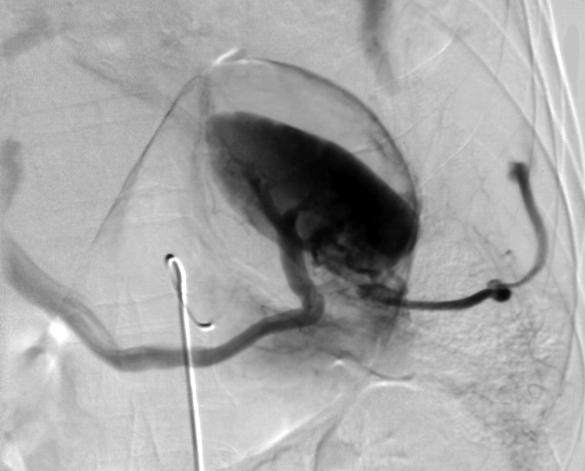

对于不稳定的病人,外科手术的策略是脾切除(splenectomy)或脾修补术(splenorrhaphy)。但究竟不稳定的病人应该直接去手术室,还是导管室?特别是符合伤,或尚不能决定出血的来源患者。对于稳定的病人非手术治疗的策略应该是卧床休息、观察、CT,和明确脾损伤的情况下酌情栓塞。 决定者还要考虑的是附带损伤(collateral damage)如肠道损伤,胰腺损伤等。诊断性腹腔灌洗(diagnostic perito-neal lavage,DPL)和各种稳定病人措施。是否在黄金时间快速进入导管室,还是有争论的问题。另一个需要关心的病人是非出血病人的延迟出血(later bleeding)。可能对NOM有效的病人,初始与临床表现相一致的CT表现(Shanmuganathan et al Radiology 217:75, 2000;Davis et al J Trauma 44:1008, 1998;Bee et al J Trauma 50:230, 2001)并不意味着日后不出血,24小时-72小时重复CT扫描,血管损伤可能并不是最初的表现。 ![]() 172例有CT证据的脾损伤,150例为稳定患者进行了非手术处理(NOM);60例弹簧栓子栓塞患者中56例获得成功(Sclafaniet al J Trauma 39:818, 1995)。 栓塞技术 根据栓塞水平,有两种主要的脾动脉栓塞技术【5】。近端脾动脉栓塞技术和超选择远端脾动脉栓塞技术。 (1)近端脾动脉栓塞技术

病例1:近端脾动脉栓塞

病例2

病例3

病例4:近端脾栓塞后胰腺侧支循环形成

13例钝性创伤,近端脾动脉栓塞术,远端到胰背动脉,近端到胰大动脉,阻塞过程需要10分钟,3例外加弹簧栓子。1例后来进行脾切除,其它脾保留(Widlus et al. JVIR 2008)